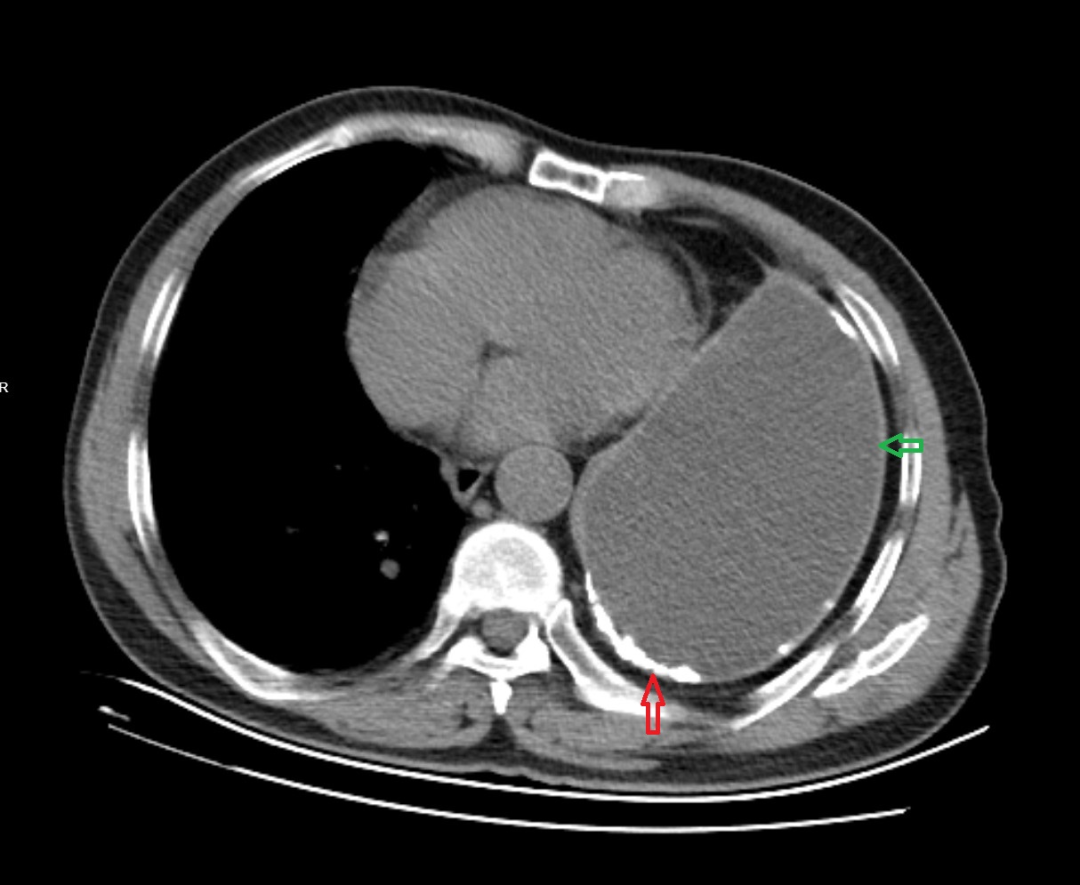

胸部CT示两肺及肋骨平扫未见明显挫伤征象,左侧胸腔包裹性积液并胸膜增厚、钙化,左肺不张(见图1-图4)。

1. 绿色箭头:左侧大量胸腔积液。

4. 绿色箭头:左侧胸腔积液;红色箭头:左侧胸膜增厚、钙化。